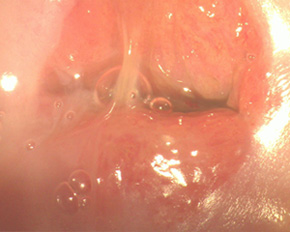

Лікування ерозії шийки матки: пацієнт П